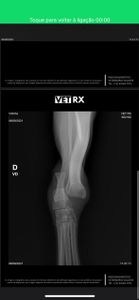

Ela foi salva por moradora local e está em recuperação, mas precisa de cirurgia urgente para reparar uma pata quebrada.